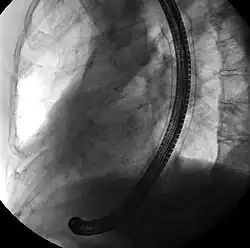

![]() Endoscopic view of a self-expandable metallic stent used to palliate an esophageal cancer | |